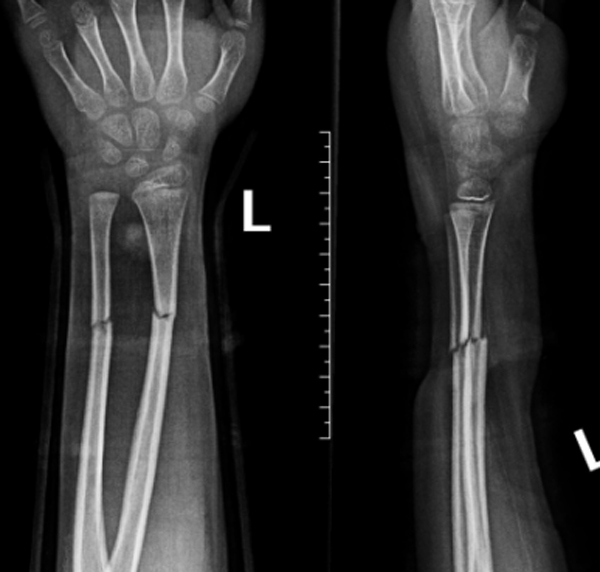

伤后15天复查

伤后25天复查

复位后,医护团队为家属详细指导护理事项,并制定系统复查计划。在随后数周的跟踪随访中,患儿骨折位置维持稳定,未出现移位。直至拆除夹板之日,其左前臂功能已基本恢复,骨骼愈合近乎完美。